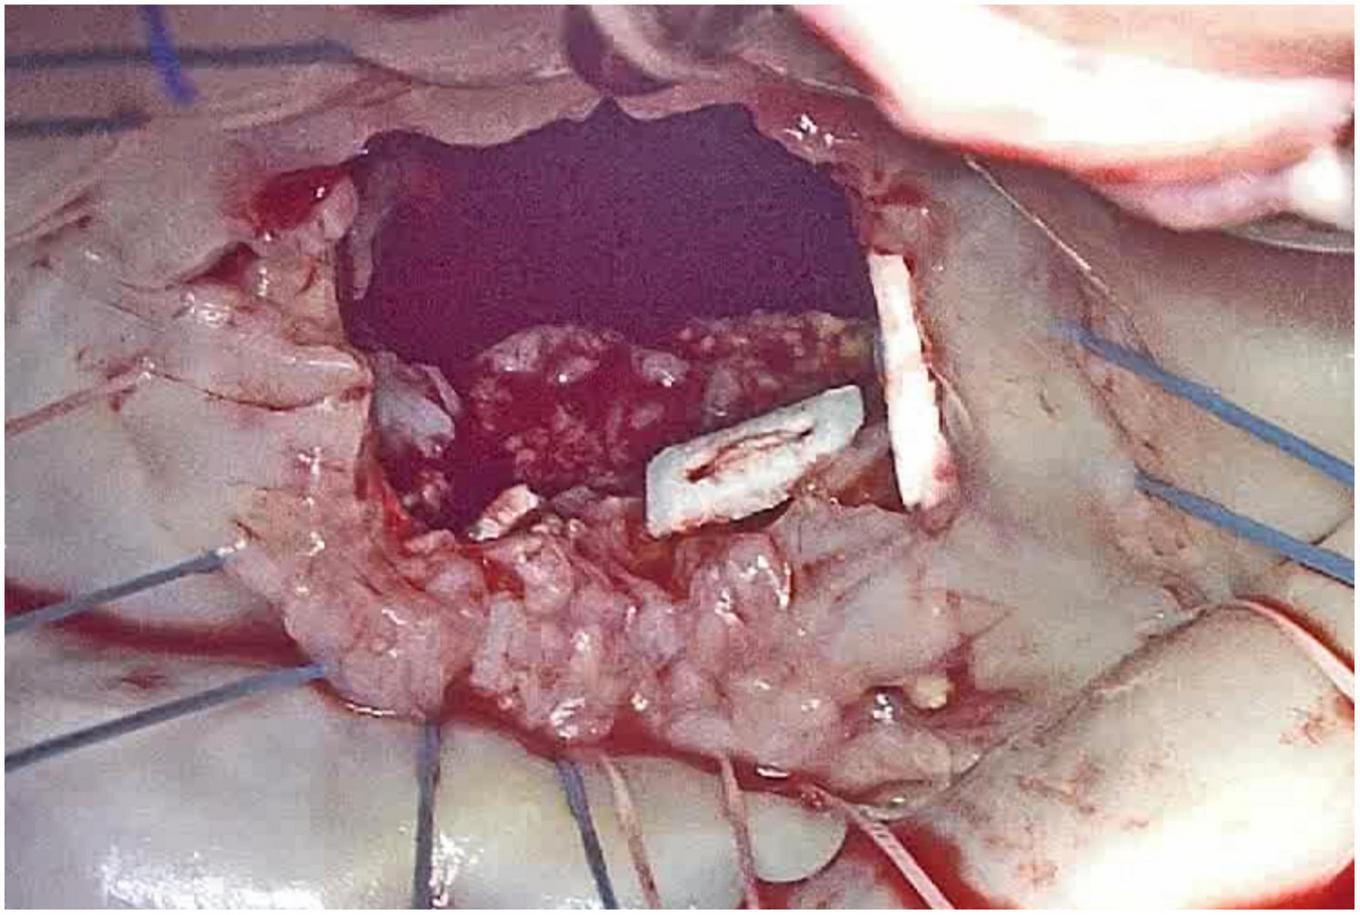

Surgical mitral valve repair or replacement remain the gold standard to treat patients with mitral valve pathology, even in presence of severe MAC (Figure 3).

FIGURE 3

Intra-operative appearance of mitral annular calcification (MAC) during surgical inspection, after anterior mitral leaflet removal.